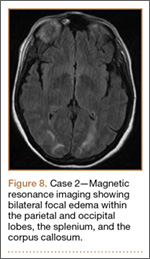

Development and Diagnosis of PRES. The patient was ambulatory with physical therapy and a walker on postoperative day 1. Her albumin levels were noted to be decreased postoperatively (28 mg/mL; normal, >35 mg/mL). She developed intermittent hypertensive episodes and experienced transient peripheral vision loss. After her ophthalmologic symptoms cleared, she was discharged and transferred to a rehabilitation facility on postoperative day 9. Eleven days later, the patient was emergently readmitted for a deep spine wound infection after an onset of wound swelling and fever. She underwent irrigation and débridement of the spine wound with an estimated blood loss of 400 mL. The patient continued to have fevers and was placed on ciprofloxacin and vancomycin, which was changed to levofloxacin on postoperative day 5. Elevated creatinine was noted, and the patient was diagnosed with acute renal failure. On postoperative day 7, oxacillin therapy was commenced. After her cultures grew methicillin-resistant Staphylococcus aureus, a peripherally inserted central catheter line was placed on postoperative day 9. As a result of nausea and constipation, the patient received feeding tubes on postoperative day 11. Additionally, she was diagnosed with a pleural effusion on postoperative day 14. Although her creatinine levels were decreasing, she continued to experience intermittent hypertensive episodes with a mean peak systolic blood pressure of 148 mm Hg. On postoperative day 15, she had a seizure and again developed visual loss. The patient was lethargic and followed only simple commands. She moved all extremities and withdrew symmetrically to noxious stimuli. Upon emergent imaging, head CT showed posterior subcortical white matter hypodensity within the occipital and parietal lobes bilaterally (Figure 7). MRI showed focal regions of symmetric hemispheric edema involving the parietal and occipital lobes in a predominantly subcortical white-matter distribution. Additionally, extensive involvement of the splenium and of the corpus callosum, left greater than right, was observed (Figure 8).